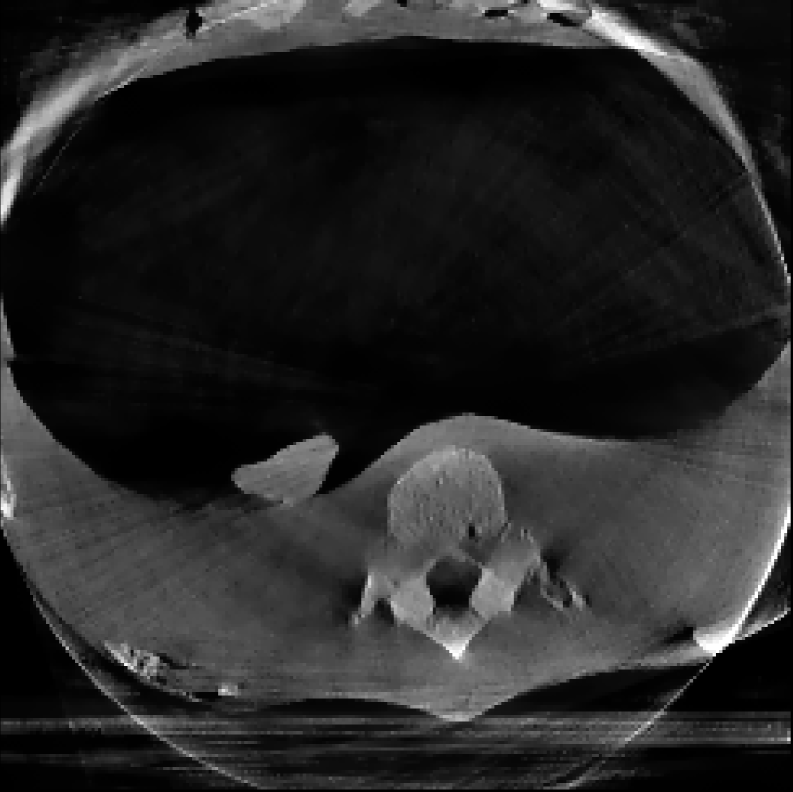

3.2 Lung Needle Surgery Scan:

In this example, we reconstruct a Thorax phantom scanned using the Phillips Allura FD20 Xper C-arm CBCT scanner. This device has source-to-axis and source-to-detector distances of 810 mm and 1195 mm respectively, and an installed detector of size 30×\times40 cm2 with 0.776 mm pixel pitch. Moreover, the data has a resolution of 364×512×364\times 512\timesnumber of projections and the image is reconstructed with a resolution of 256×256×256256\times 256\times 256 voxels.

The reconstructions corresponding to the real-scan data with different number of projections (180, 50, and 20, respectively), can be observed in Figures 3, 4, and 5. In all three figures (a) is the prior image 𝒙p\boldsymbol{x}_{p} used for prior image regularization, (f) is the ground truth image; and the rest of images correspond to different reconstructions (top) with their corresponding errors (bottom). Analogously to the previous experiment, the difference images (or error) should be completely black in the case of a perfect reconstruction and high intensity indicates more inaccurate reconstructions.

Note that the real data contains a lot of measurement noise, and due to the presence of the needle, the reconstructions can suffer from strong metal artifacts. Therefore, the reconstructed images using different algorithms, particularly without explicit regularization, tend to show strong errors even with a high number of projections. Accordingly, all the algorithms with explicit regularization perform better in this scenario, and particularly those including PIPLE or PICCS regularization. Moreover, the proposed IRN-PIPLE algorithm significantly outperforms other methods, and IRN-PICCS is not far behind. Using only TV regularization struggles to separate artifacts from features, oversmoothing images and thus loosing important image features. Notably, the proposed methods reconstruct high quality images in less than 2 minutes in an implementation that is not optimized to solve this specific geometry.

Figure 4: Reconstructed images using real measurements of a thorax phantom with 50 projection. The reconstructed images are shown in [0, 0.03]; difference images in [–0.04, 0.04].